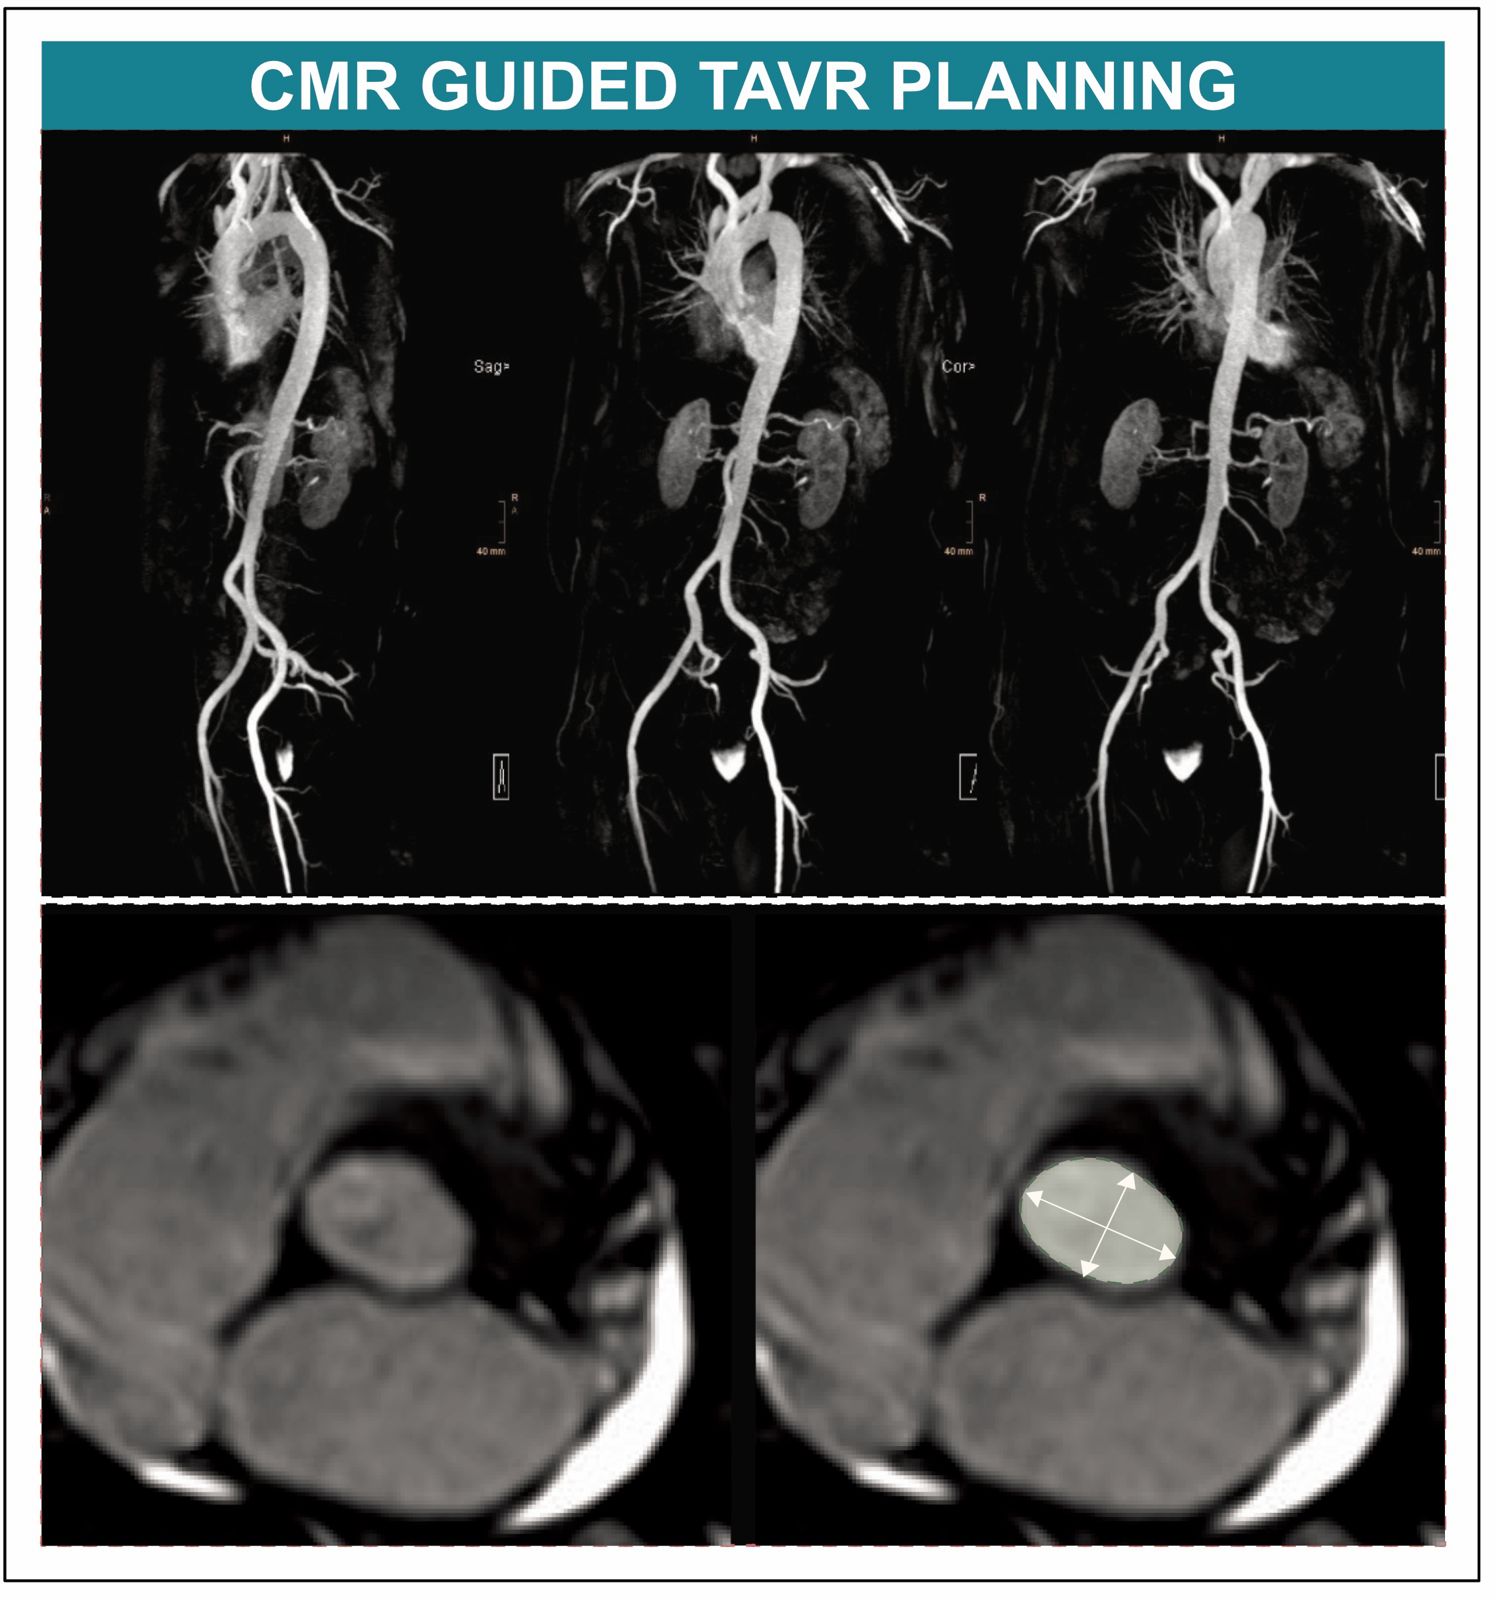

Die prä-interventionelle Planung des Eingriffes erfolgt üblicherweise mittels Computertomografie (CT), was für Patient:innen mit Niereninsuffizienz aufgrund des erforderlichen Einsatzes von iodhaltigem Kontrastmittel allerdings eine wesentliche Einschränkung darstellt.  „Rund die Hälfte aller TAVI-Kandidatinnen und -Kandidaten leidet an einer Niereninsuffizienz und ist durch den Einsatz jodhaltiger Kontrastmittel im Rahmen einer CT einem erhöhten Risiko für eine Nierenschädigung ausgesetzt. Die Strahlenbelastung im Rahmen des CTs ist ein weiterer Nachteil, vor allem im Lichte der immer jünger werdenden TAVI-Population“, weiß Sebastian Reinstadler von der Innsbrucker Univ.-Klinik für Innere Medizin III (Kardiologie und Angiologie). Agnes Mayr von der Innsbrucker Univ.-Klinik für Radiologie ergänzt: „Die kardiale Magnetresonanztomographie (CMR) bietet sich als vielversprechende strahlenfreie Alternative an, bislang fehlten jedoch randomisierte Daten zum Vergleich der Tauglichkeit von CMR- und CT-gesteuerter TAVI“.

BU: Neue Daten belegen, dass die Kardioale Magnetresonanztomografie bei der Planung einer TAVI keine Nachteile hat. (c)Kardiologie Innsbruck

In einer neuen, kürzlich im anerkannten Fachjournal Circulation veröffentlichen Studie konnte nun erstmals die CMR als gute und klinisch geeignete Alternative für die TAVI-Planung nachgewiesen werden. Für das Kooperationsprojekt zwischen der Univ.-Klinik für Kardiologie und Angiologie und der Univ.-Klinik für Radiologie wurden TAVI-Kandidat:innen an den Herzzentren in Innsbruck und Wels randomisiert und einer CMR-gesteuerten oder einer CT-gesteuerten TAVI-Planung zugeführt. „In der Kohorte mit jenen Patient:innen, die sich einer TAVI unterzogen hatten, konnten wir feststellen, dass die CMR-gesteuerte TAVI der CT-gesteuerten TAVI im Hinblick auf den Implantationserfolg nicht unterlegen war und daher als Alternative zur TAVI-Planung in Betracht gezogen werden kann“ bestätigt Erstautor Martin Reindl, der diese positiven Erkenntnisse gemeinsam mit der von Bernhard Metzler geleiteten Arbeitsgruppe Kardio-MRT am diesjährigen ESC Kongress, dem weltweit führender Kongress im Bereich Kardiologie, in der prominenten „Late Breaking Science“ Session vorstellen konnte.